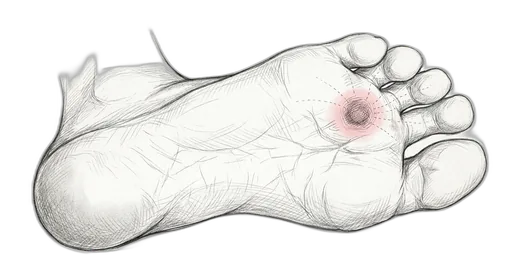

Morton's Neuroma

At a glance: A Morton's neuroma is a thickening of the tissue around a nerve that runs between the metatarsal heads, most commonly between the third and fourth toes. It's not actually a tumor — it's a perineural fibrosis caused by chronic compression and irritation. The result is sharp, burning, or electric-shock pain in the ball of the foot that often radiates into the toes. Wider shoes, metatarsal pads, and the strengthening exercises here can reduce the compression on the nerve.

Understanding Morton's Neuroma

Between each metatarsal head, a small nerve (common digital nerve) passes through a tight space. When the metatarsal heads are squeezed together — by narrow shoes, high heels, or an unstable forefoot — the nerve gets pinched repeatedly. Over time, the nerve develops protective scar tissue around it, which makes it bulkier and even more prone to compression. It's a vicious cycle. Patients often describe the feeling as stepping on a marble or a bunched-up sock, or a sudden electric zap that makes them stop and take their shoe off. The exercises in this program help by spreading the toes and strengthening the transverse arch to give the nerve more room.